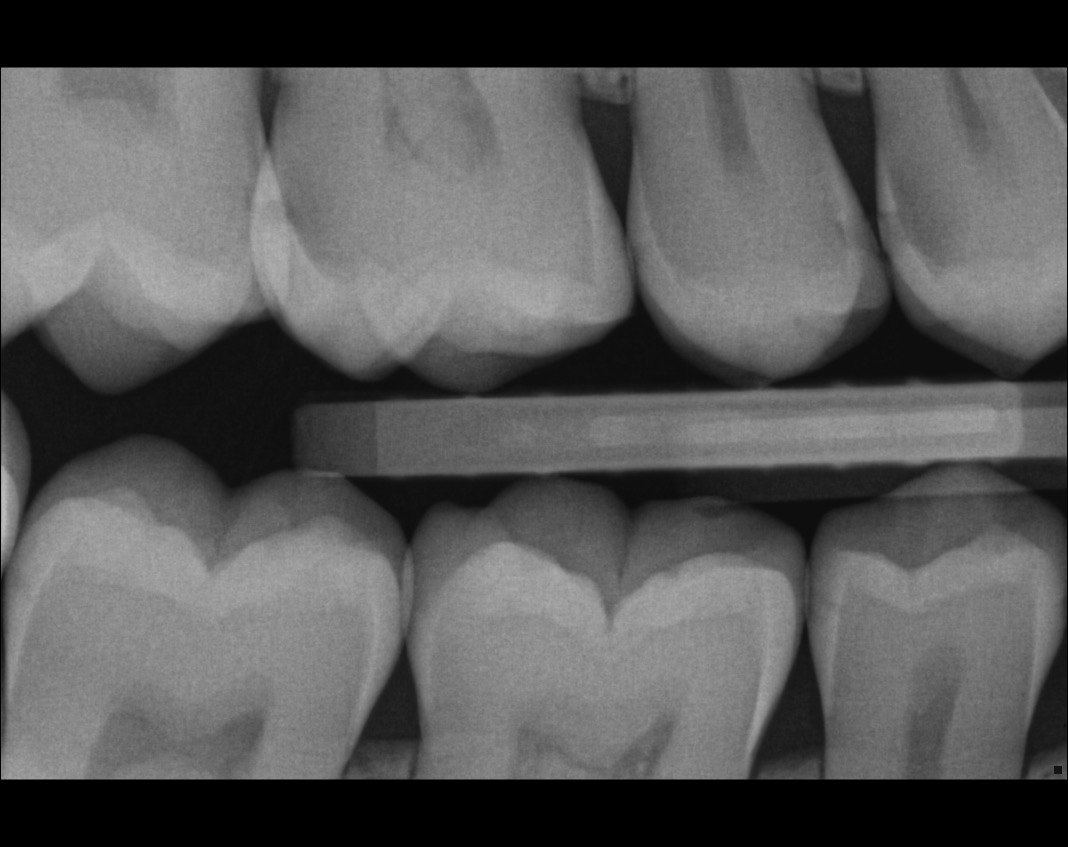

Question 4: what is the condition of the distal of the tooth # 4.1 and mesial of the tooth #3.1 respectively?

Question 5: Which surface shows recurrent caries?

Question 6: Which surface shows recurrent caries?

Question 7: What are the options associated with the distal surface of the tooth # 2.1 and mesial surface of the tooth # 2.2 respectively?

Question 8: What is the condition associated with the occlusal surface of the tooth # 1.6?

Question 9: What is the condition associated with the mesial and distal surfaces of the tooth # 1.4 respectively?

Question 10: What is the condition of the distal surfaces of the teeth # 1.5 and 1.6 respectively?

Quistion 11: What are the conditions of the distal and mesial surfaces of the tooth # 4.5 respectively?

Question 12: What option can describe the mesial surface of the tooth # 3.7?

Question 13: What option can describe the mesial surface of the tooth # 3.8?

Question 14: What option can describe the mesial surface of the tooth # 3.4?

Question 15: What option can be selected for treatment of the caries in mesial surface of the tooth # 3.4?

Question 16: What option can be chosen for the treatment of the mesial surface of the tooth # 3.7?

Question 17: What are the caries extention in distal of the tooth # 2.4 and mesial surface of the tooth # 2.5 respectively?

Question 18: What is the option that can describe the distal surface of the tooth # 1.7?

Question 19: What is the option that can describe the mesial surface of the tooth # 1.8?

Question 20: What is the option that can describe the distal surface of the tooth # 4.5?

Question 21: What options can describe the mesial and distal surfaces of the tooth # 4.7 respectively?

Question 22: What codition cannot be seen in the lower teeth in this X ray?

Question 23: What option can describe the distal surface of the tooth # 4.5?

Question 24: Which condition can be detected in the following X ray?

Question 25: What treatment is appropriate for distal surface of the tooth # 3.4 and mesial surface of the tooth # 3.5?

Question 26: What is the option explaining the distal surface of the tooth # 2.6 and mesial surface of the tooth # 2.7 respectively?

Question 27:  What is the option explaining the distal surface of the tooth # 2.5 and distal surface of the tooth # 2.4 respectively?

Question 28: What is the option explaining the distal surface of the tooth # 2.5?

Question 29: What is the option explaining the Mesial surface of the tooth # 2.5 and distal of tooth # 2.4 respectively?